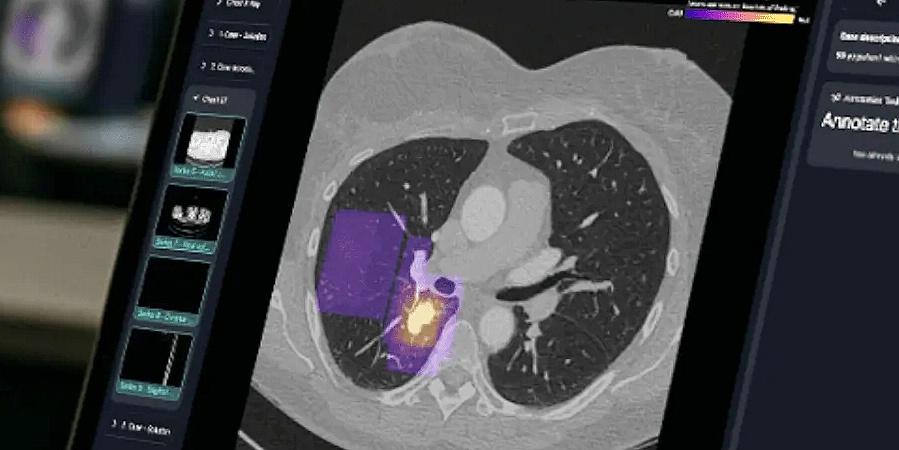

Genau hier setzt das prämierte Projekt „Befundung neu erleben: Interaktive Radiologie-Lehre für die Zukunft“ an. “Wir wollen den entscheidenden Schritt von der passiven Betrachtung zur aktiven, diagnostischen Analyse gehen”, so Sebastian Tschauner, Leiter der Klinischen Abteilung für Kinderradiologie der Med Uni Graz. Kernstück des Projekts ist die Implementierung der neu entwickelten, webbasierten Plattform rapmed.net in die Lehre des Moduls „Bildgebung und Biostatistik“. Die Anwendung ermöglicht es seit Kurzem, den nächsten Evolutionsschritt zu gehen: Komplexe Schnittbildverfahren wie CT und MRT werden in Echtzeit von der*dem Vortragenden auf die Endgeräte aller Studierenden im Raum verteilt. Diese können sich per QR-Code einloggen und auf ihrem eigenen Smartphone, Tablet oder Laptop den vorgestellten Fall bearbeiten – so, als säßen sie an einer echten kleinen Workstation. Sie können durch die Schichten der jeweiligen Untersuchung scrollen, pathologische Veränderungen direkt im Bild markieren und ihre Verdachtsdiagnose über interaktive Quizformate abgeben.

Durch Echtzeit-Feedback und „Gamification“-Elemente, wie etwa eine Konsensus-Karte, die anzeigt, in welchen Bereichen einer Untersuchung die Mehrheit der Student*innen eine Pathologie vermutet, wird der Lernprozess dynamisch und motivierend. Sowohl vonseiten der Lehrenden als auch der Studierenden kann detaillierter auf die charakteristischen Befunde und Merkmale einer Erkrankung eingegangen werden. Dies fördert nicht nur das Erkennen von Krankheitsbildern, sondern schult auch die diagnostische Kompetenz auf eine praxisnahe und nachhaltige Weise. Das Projekt ist mehr als nur der Einsatz einer neuen Software. Es ist ein didaktisches Gesamtkonzept, das auch mehrere Ziele der universitären Strategie in die Praxis umsetzt.